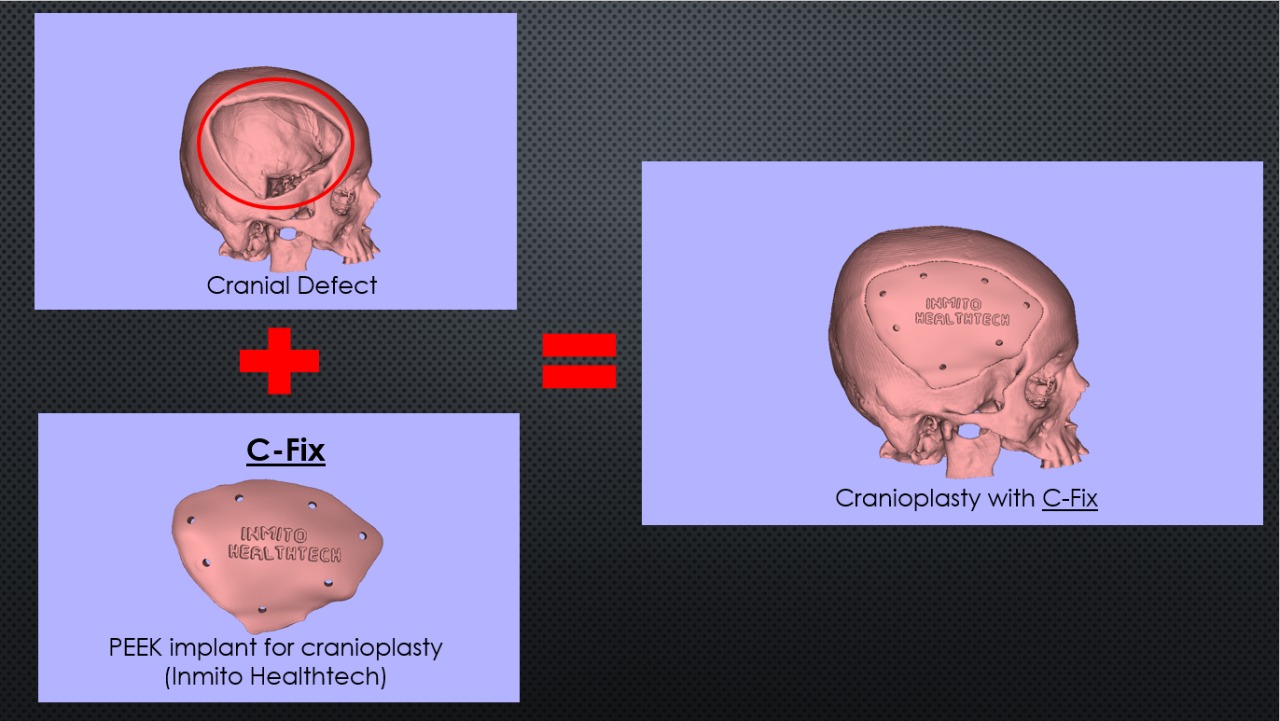

C Fix Patient-specific PEEK implants are the latest & best in class solution for cranial reconstruction in cranioplasty.

C Fix is designed in collaboration with neurosurgeons & made to fit the specific requirement of a patient. It is manufactured considering each patient’s anatomy and intraoperative adaptation & ease of use. Anatomical perfection is the goal of reconstruction surgery & C Fix helps achieve that.

Custom Cranial Implants are combined products of medicine, design, and engineering. It’s an example of a modern-day collaborative approach to addressing case basic solutions to patient needs. The goal is to have functionality & aesthetics with no compromise of one for the other.